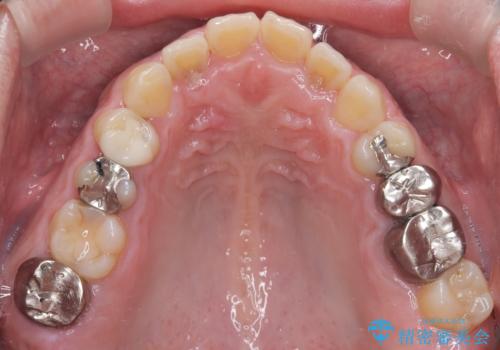

- お口の中にある銀歯を全てなくして、白く健康的な状態にしたい」という主訴でご来院されました。長年使用してきた複数の銀歯は、経年劣化により適合が悪くなっており、一部では内部で二次カリエス(虫歯の再発)も認められました。

患者様と相談の上、全ての金属(メタル)を取り除き、生体親和性が高く審美性に優れた素材へ置き換えるメタルフリー治療の計画を立案。部位や欠損の大きさに合わせ、セラミックインレーおよびセラミッククラウンを用いて、お口全体の調和を整えることとしました。

銀歯の除去と精密な再治療: 古い銀歯を一つひとつ丁寧に取り外し、内部の虫歯を徹底的に除去。神経を保護するための処置を行った上で、適合性を極限まで高めるために精密な型取りを行いました。

オールセラミックによる修復: 天然歯のような光の透過性と硬さを持つオールセラミックを使用しました。奥歯であっても、患者様固有の歯の色調や咬み合わせの溝を忠実に再現した修復物を装着。金属を一切使用しないことで、金属アレルギーのリスクを排除し、歯肉の色が黒ずむ心配もなくなりました。